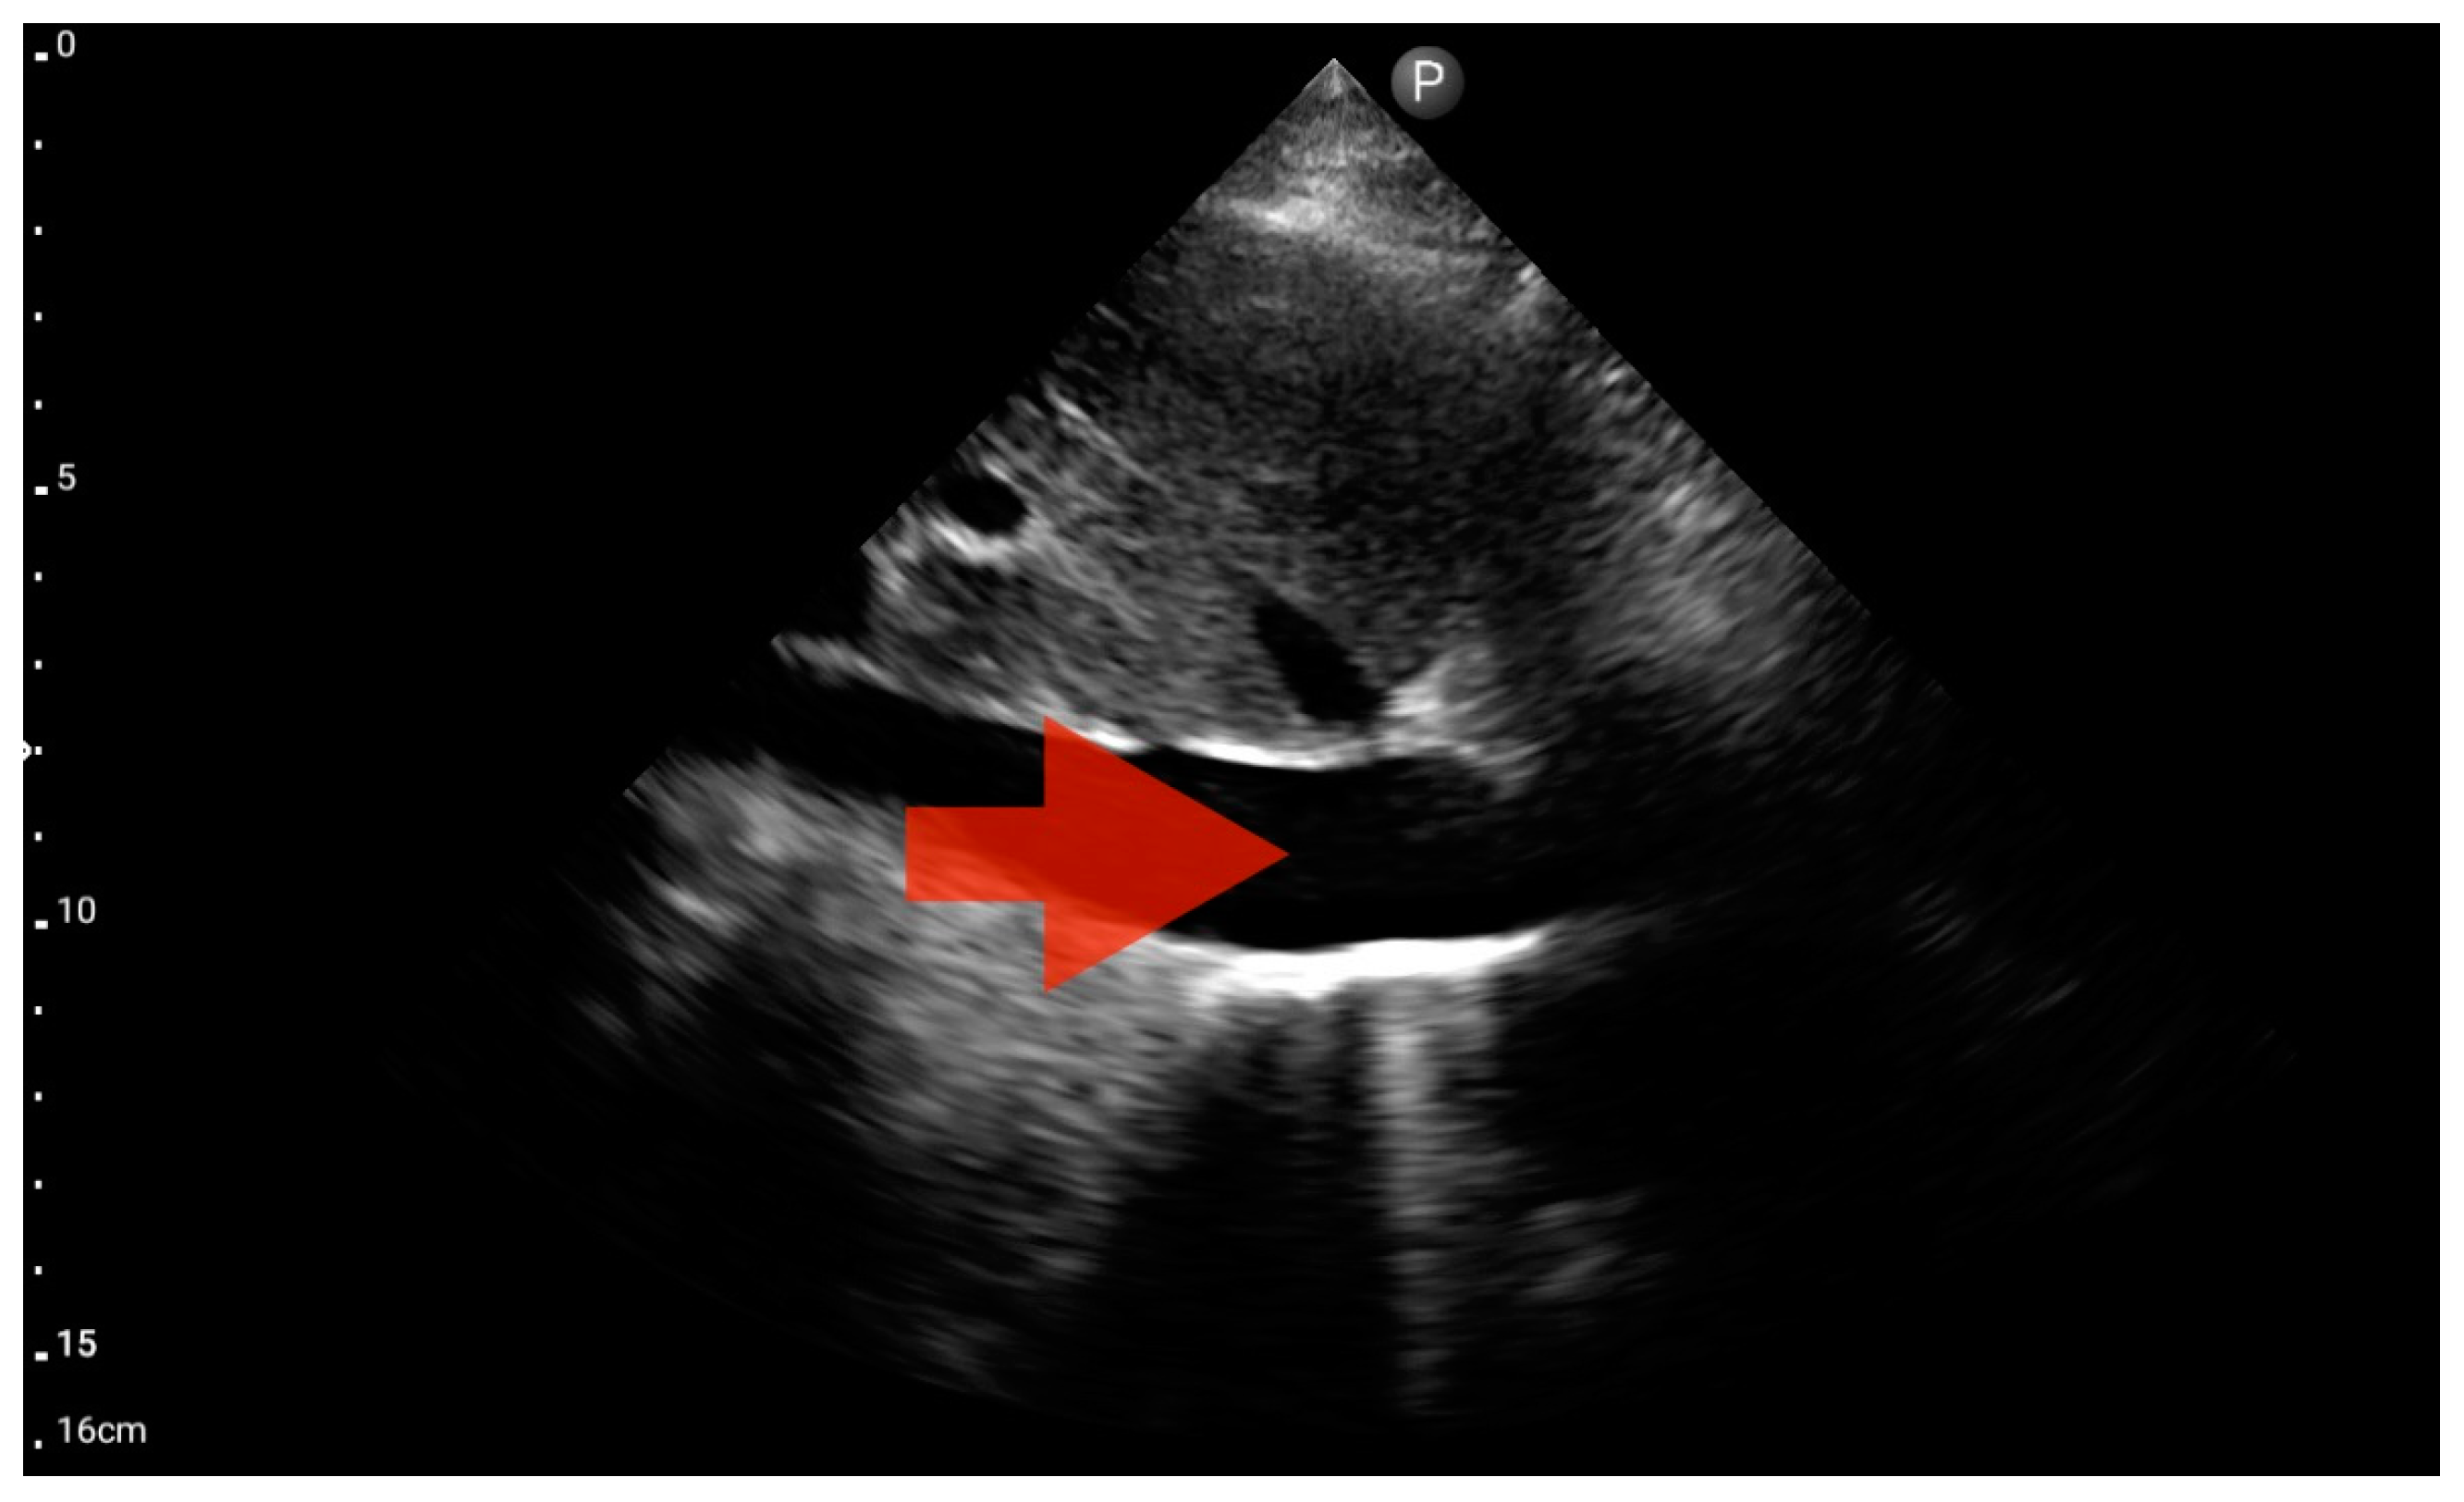

Other detected pathologies, including left ventricle enlargement (2 patients; 12.5%) (Figure 12), right ventricle enlargement (2 patients; 12.5%) (Figure 13) and pericardial effusion (1 patient; 6.25%) (Figure 14), were observed only incidentally. Therefore, further validation in a larger-scale study is warranted to analyze the significance of these symptoms in the pre-hospital setting.

Figure 12.

Left ventricle hypokinesis; position: apical four-chamber (FATE protocol). Sector probe; the red arrow marks the left ventricle, which, during the examination, showed signs of reduced ejection fraction and hypokinesis (source: author’s material—DK).